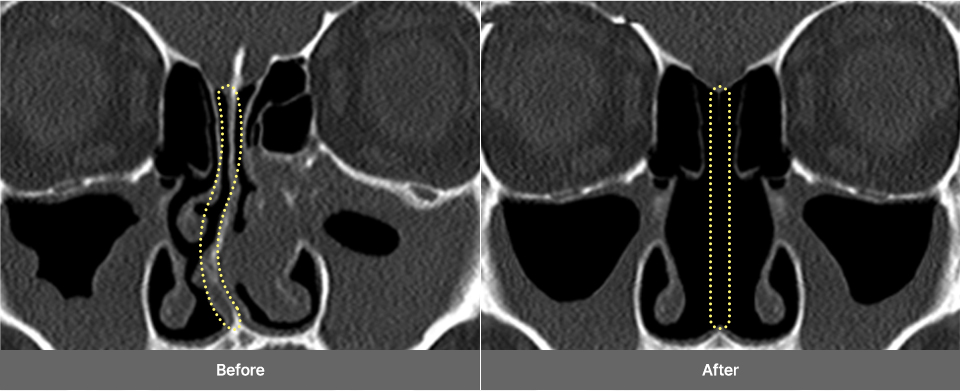

Deviated Nasal

Septum

A deviated nasal septum

occurs when

the cartilage

located at the center of

the nose bends, causing

functional

issues such

as nasal congestion,

rhinitis, and sinusitis.

Treatment Points

Remove the curved septal

cartilage and bone, then

straighten the septal

cartilage

to correct the

shape properly.

3D-CT and Precision

Nasal Endoscopy

3D-CT Examination

Before surgery, a 3D-CT scan is conducted to accurately capture internal

nasal structures, including the skeletal structure, nasal bone width, septal

condition, asymmetry, and inferior turbinate size, which are difficult to

observe with the naked eye